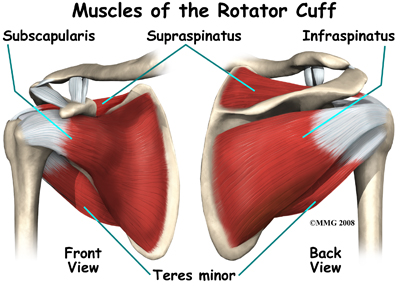

The rotator cuff connects the humerus to the scapula.

Four muscles and their associated tendons form the rotator cuff: the supraspinatus, infraspinatus, teres minor, and subscapularis.

Tendons attach muscles to bones. Muscles move the bones by pulling on the tendon that they attach to. The rotator cuff muscles help raise and rotate the arm. As the arm is raised, the rotator cuff also keeps the humerus tightly in the socket. The socket of the shoulder is part of the scapula bone and is called the glenoid fossa. The glenoid fossa is very shallow and flat so without the rotator cuff muscles the top part of the humerus (the head) would slide out of the centre of the fossa.

Rotator cuff problems are common conditions in the shoulder, especially as we grow older. Degeneration or wear and tear of the rotator cuff tendons occurs as we age. Over time this can lead to weakening of the tendons and may result in a rotator cuff tear.

Surgery to repair a rotator cuff tear is fairly common in people who are middle aged or older. Small, medium and many large tears can be repaired either through arthroscopic or open surgical procedures. Most rotator cuff repairs are successful but in a portion of patients the torn tendon has become so degenerated that the tendon cannot be repaired. Unfortunately, many large tears that are untreated for a long time may retract which renders them unfixable.

A shoulder joint without an intact rotator cuff may still function relatively well. Some patients will have some weakness, pain and may not be able to completely raise the arm, however, they get by without full function of their rotator cuff fairly well. There are many people who choose not to have surgery to repair a rotator cuff tear and will simply live with the limitations. Patients with massive rotator cuff tears, however, may not be able to lift the arm without significant pain and weakness, which severely limits them on a daily basis. When the arm cannot be lifted, this is called a pseudoparalytic shoulder.

A normal functioning rotator cuff helps to keep the shoulder stable so that it can move well, and also helps to create part of the joint capsule, which holds the joint fluid that lubricates the joint. Over time, a shoulder without an intact rotator cuff becomes arthritic; the shoulder joint wears out due to the abnormal motion in the joint, the instability, and the decreased joint fluid lubrication. This type of wear and tear arthritis in the shoulder is called (rotator) cuff tear arthropathy.